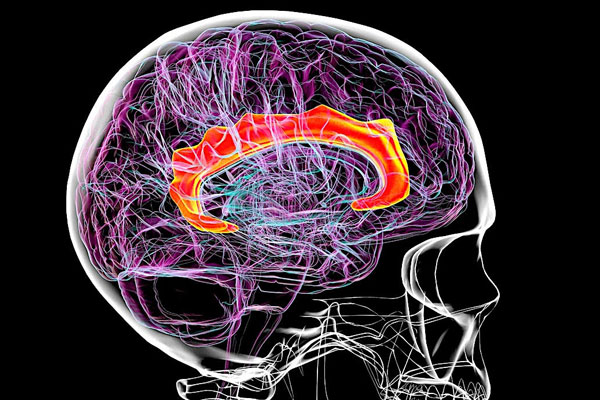

Jan. 16, 2026 – A sweeping new study of psychiatric and genetic records has the potential to change treatment for millions of psychiatric patients, finding that many conditions involve similar genes and may not need to be treated as distinct illnesses. In essence, the study suggests that bolstering the traditional emphasis on patient behavior with a deeper understanding of the biology of mental illness could lead to better treatment.

Published in Nature, the paper addresses the boundaries psychiatry uses to separate similar conditions like bipolar disorder and schizophrenia. The research also suggests that linking genes to the brain processes they influence will provide psychiatrists with greater insight into their patients, and guide researchers toward new therapies.